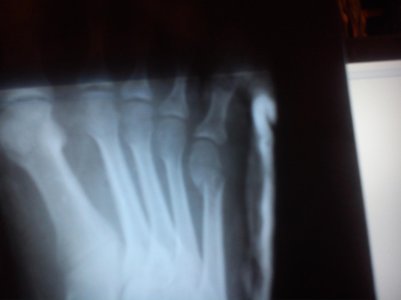

Рентген 17.04

Рентген11.05